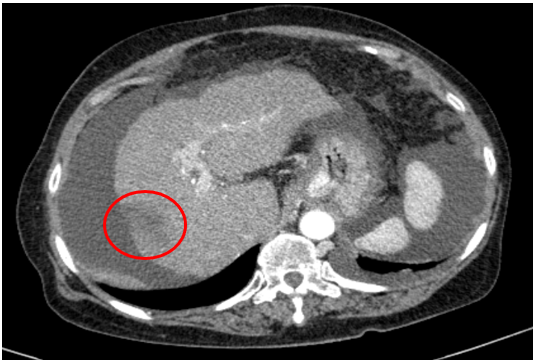

Chụp cắt lớp vi tính ổ bụng

Gan: biến đổi hình thái, bờ không đều. Nhu mô gan phải có khối giảm tỉ trọng kích thước 26x25mm, ranh giới không rõ, co kéo bao gan lân cận,trong có hình ảnh tăng tỉ trọng của vật liệu nút mạch, sau tiêm có phần ngấm thuốc ngấm thuốc.

Dịch quanh gan 8mm., dịch tự do ổ bụng

=> Hình ảnh u gan phải sau điều trị hiện còn phần ngấm thuốc (Vòng tròn đỏ) /Xơ gan